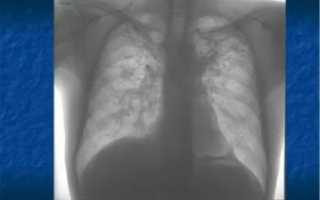

Для визуализации патологического процесса назначается рентгенологическое исследование органов грудной клетки, которое позволяет обнаружить изменения в легких. Обнаруживаются изменения с обеих сторон, преимущественно в нижних отделах легких.

Отмечаются усиление и деформация легочного рисунка, постепенно формируется картина так называемого «сотового легкого», которое характеризуется образованием кольцевых теней диаметром 3 – 7 мм со стенками толщиной до 3 мм, что в некоторой мере напоминает пчелиные соты.

Более детальную оценку структурного состояния легких дают компьютерная томография (КТ) и магнитно-резонансная томография (МРТ). В тяжелых случаях, когда вышеперечисленные методы исследования не позволяют выставить правильный диагноз, прибегают к помощи биопсии легкого, которая позволяет подтвердить наличие рубцовой ткани на микроскопическом уровне.